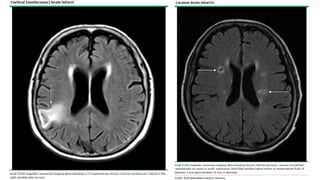

Infartos no lacunares:

• Infartos >15mm o infartos de

cualquier tamaño en corteza

cerebral.

• Pueden ser

cardioembólicos.

• Infartos corticales <5mm →

microinfartos.

Lacunas de supuesto

origen vascular:

• Infartos pequeños ≤15mm en

regiones subcorticales.

Hiperintensidades sust

blanca o

hipodensidades de

presunto origen

vascular:

• áreas > señal de agua en

sust blanca:

Desmielinización, pérdida

axones y pérdida

oligodendrocitos (imagen 4).